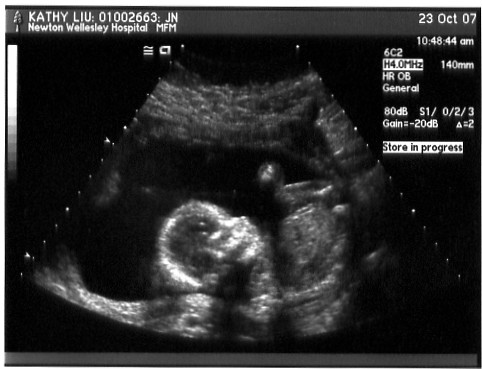

This is the follow up set of ultrasounds from Newton-Wellesley Hospital. Basically, they took a ton more measurements to look for potential signs of Downs and looked at the heart, brain, spine, etc. We also got the first guess as to the sex of our baby.

The doctor used the ultrasound wand to push down and get her to move into different positions so that all the required measurements could be taken. This shot is mostly just her head and upper torso - and perhaps a hand floating around?